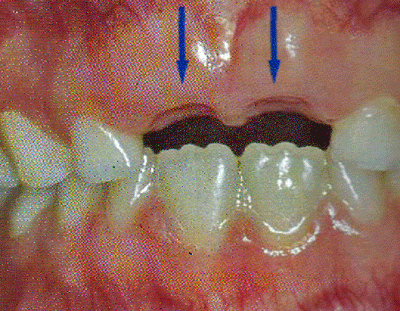

La extracción prematura del segundo molar primario (ver Fig. 7)

causará, con toda seguridad, el desplazamiento mesial del primer molar permanente y atrapará los segundos premolares en erupción. Aún cuando hace erupción el segundo premolar, es desviado en sentido vestibular o lingual hasta una posición de maloclusión. Al desplazarse mesialmente el molar superior, con frecuencia gira, desplazándose la cúspide mesiovestibular en sentido lingual, lo que hace que el diente se incline. (2)

|

Fig. 7

Pérdida Prematura del 75

Paciente Clínica Odontopediatría UGMA